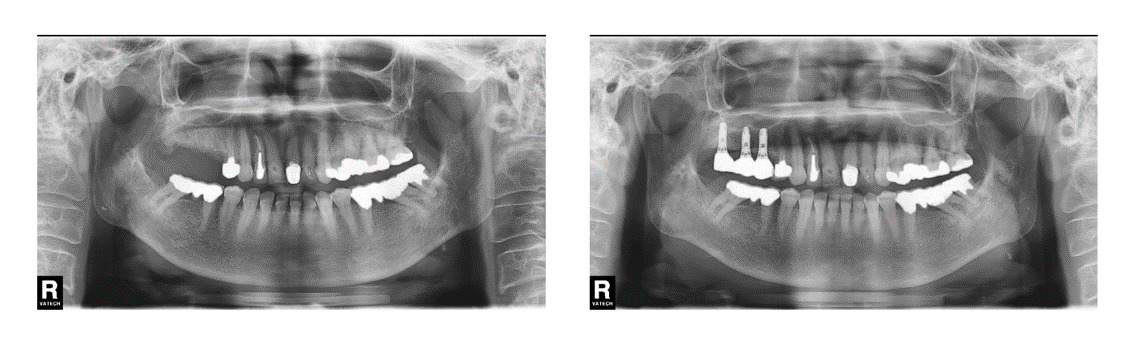

インプラント治療の症例2

(右下奥歯がない)

治療前

治療後

| 診断名・主訴 | ①右下に歯を入れたい |

| 年齢 | 41歳 |

| 治療期間 | 5ヶ月 |

| 治療内容 | インプラント治療 |

| 治療に用いた主な材料、設備機器 | 京セラFINESIAインプラント 上部構造:ジルコニアセラミック |

| 抜歯部位 | なし |

| 治療費 | 約80万 |

| リスク・副作用 | 術後出血や腫れ |

インプラント治療の症例3

(右上奥歯がない)

| 診断名・主訴 | ①右上インプラント希望 |

| 年齢 | 71歳 |

| 治療期間 | 7ヶ月 |

| 治療費 | 約100万 |